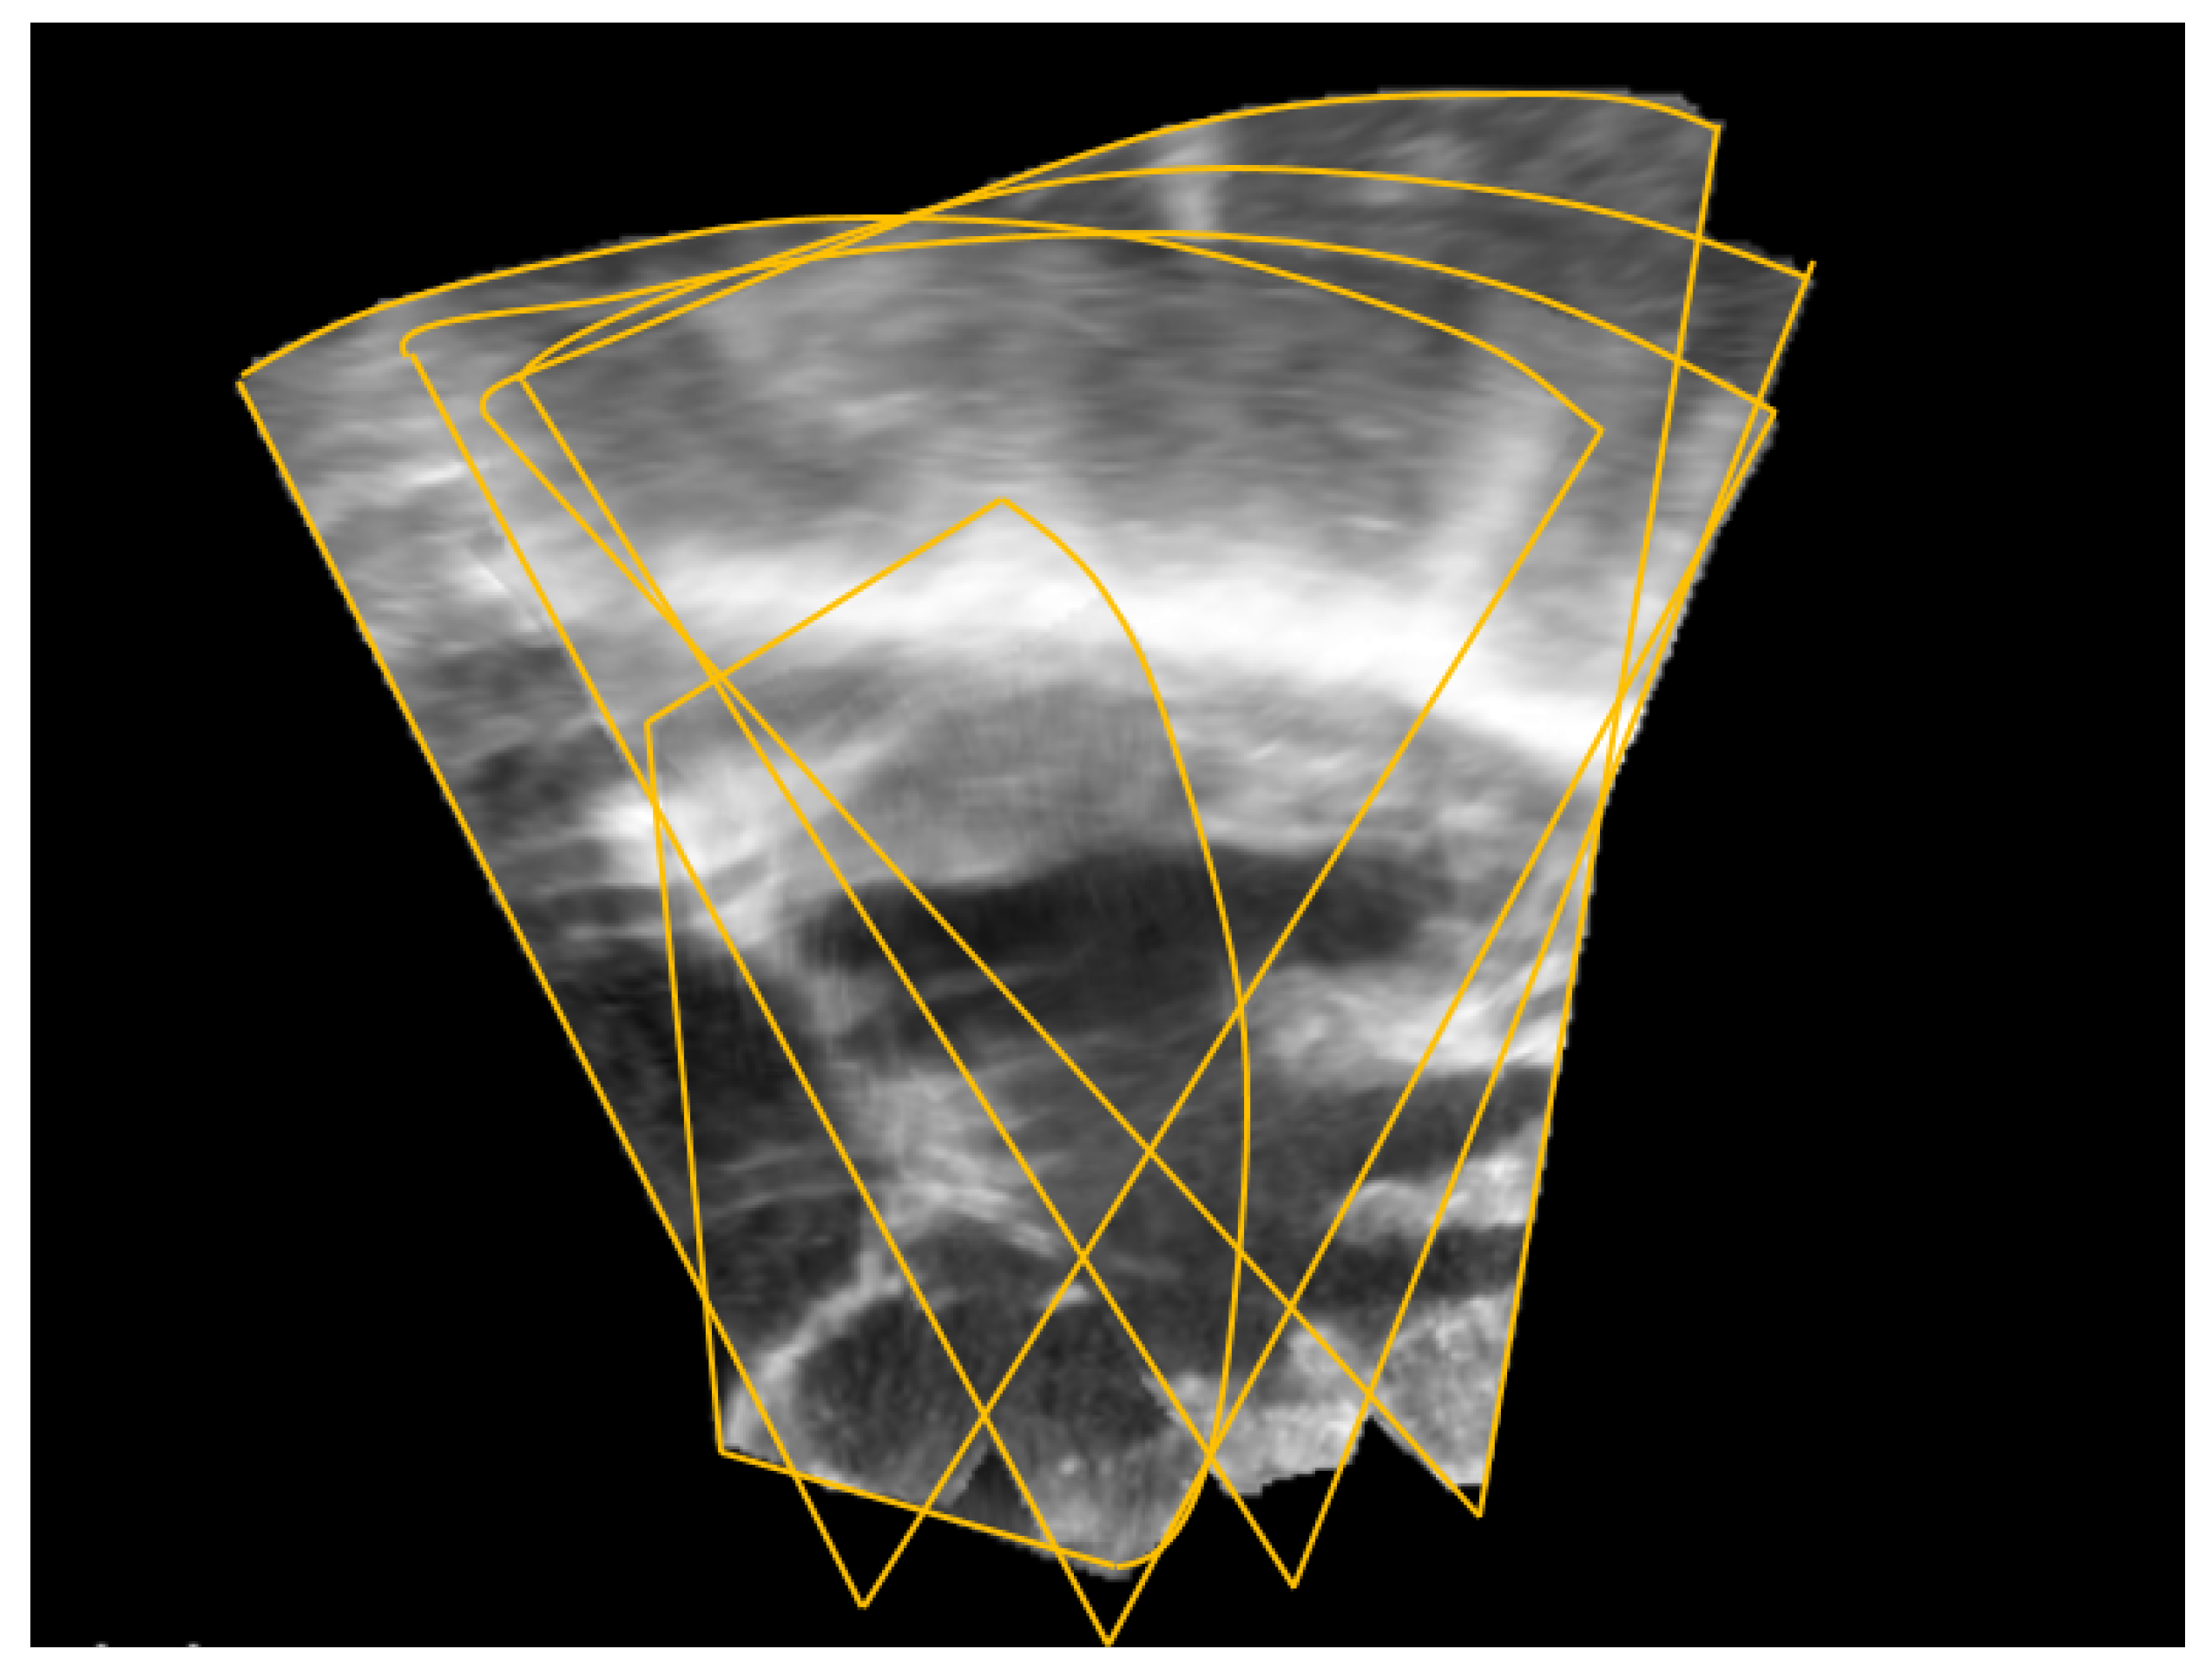

2.1. Image Registration

3.1. Porcine Model